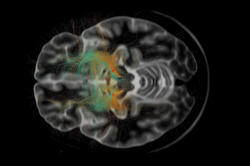

Neuer Blick auf neurologische und psychiatrische Erkrankungen

Im Exzellenzcluster NeuroCure wird Grundlagenforschung in neue Diagnosemethoden und Therapien übersetzt

Welche Impfstoffe stärken das menschliche Immunsystem? An der Charité und der Freien Universität suchen Expertenteams nach Antworten